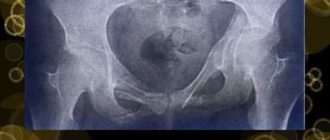

Деформация тазового кольца

Искривление таза причины, способы диагностики и лечения Искривление таза — патологическое состояние, при котором тазобедренная кость